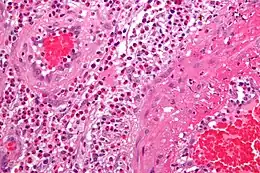

Exemple illustré : vascularites leucocytoclastiques

Le diagnostic définitif de vascularite est établi après une biopsie des organes ou des tissus impliqués, tels que peau, sinus, poumon, nerf et rein. La biopsie met en évidence le type d'inflammation des vaisseaux sanguins.

| Vascularite des petits vaisseaux cutanés | Peau, reins | Neutrophiles, nécrose fibrinoide |